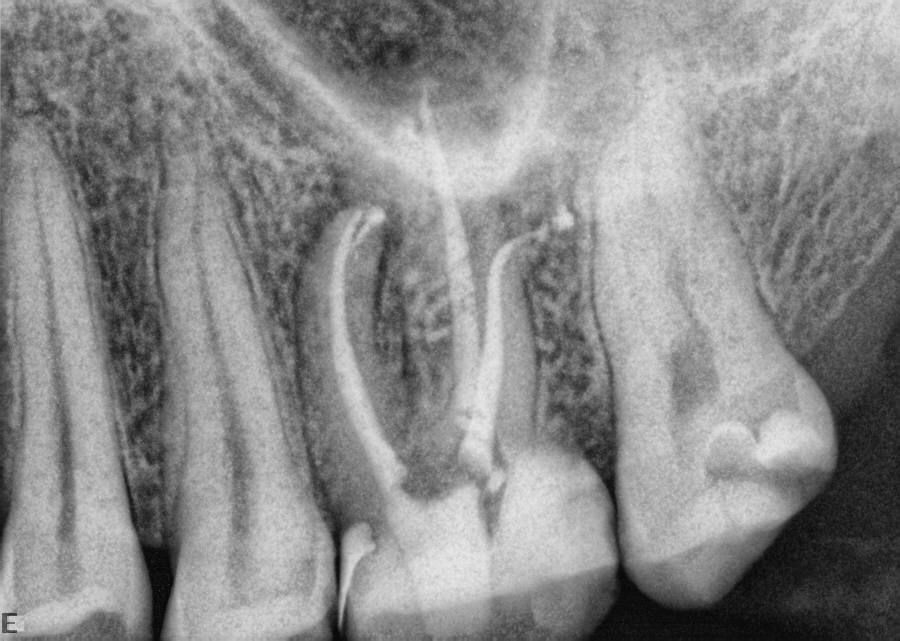

Excellent diagnosis essentially begins with two fundamental components: a doctor willing to listen to the patient’s chief complaint, and proper diagnostic tools. Among the most important tools are a precise periapical radiograph (PA) and bitewing (BW). Although a PA is often enough to provide an accurate portrayal of the patient’s condition, sometimes it alone does not suffice. Figure 1, Figure 2, and Figure 3 demonstrate a case that illustrates this point clearly. Despite two acceptable PAs (Figure 1 and Figure 2), it is difficult to assess the source of the patient’s pain to temperature. However, the BW radiograph Figure 3 provides significantly more clarity than either of the two PAs. The BW depicts localized bone loss (around tooth No. 2), a pulp stone (No. 2), a flat occlusion, numerous calcified canals, multiple restorations in tooth No. 30, and gross decay especially on tooth No. 3, which is the source of the patient’s pain to temperature. In this instance these images depict how much more useful a BW can be than just a conventional PA.